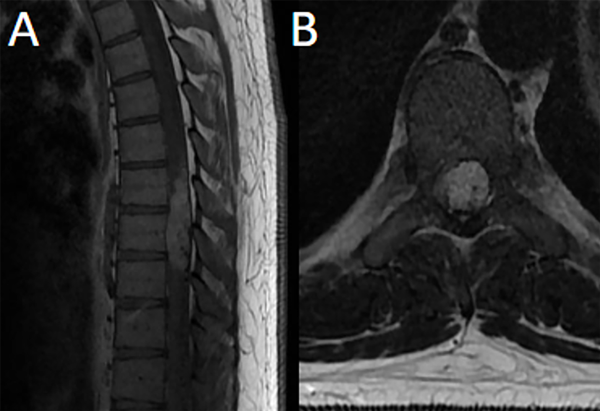

Fig 7. Caso 3. RM: T1 con contraste sagital (A) y axial (B) evidenciando lesión nodular intradural-extramedular altamente vascularizada con realce homogéneo post contraste de topografía T7-T9 que ocupa casi la totalidad del canal desplazando la médula con mielomalacia asociada.